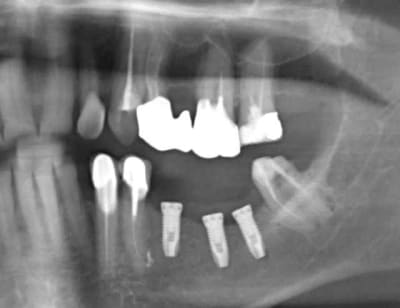

ouvre les yeux: la crétérisation est importante à 4 mois ou à un an

il y a cratérisation dans prseque tous les cas de figure: juxta ou infra-crestal.

il y a cratérisation aussi au sondage donc galère

la cratérisation apparait avec la mise en place des vis de cicatrisation

Grossière erreur lors des sutures et exposition de l'os et des implants, malgré tout on continue car belle gencive kératinisée après cicatrisation de ce bordel et résultat au bout de 2 ans ... (entre temps 38 a été virée)